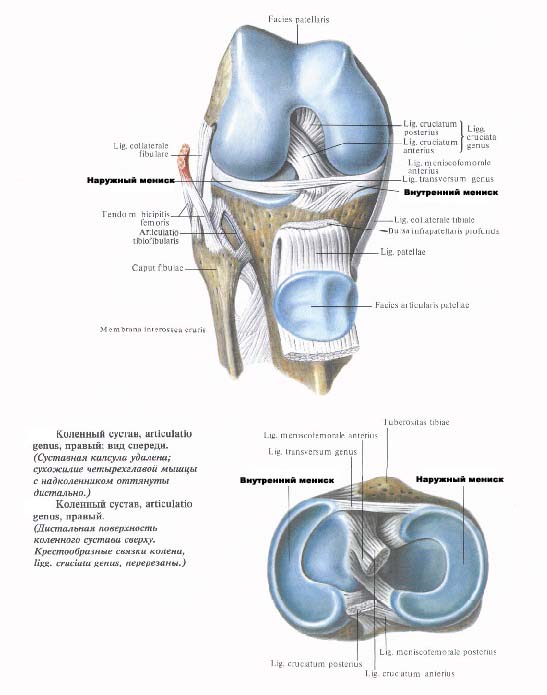

Анатомические изображения менисков и коленного сустава